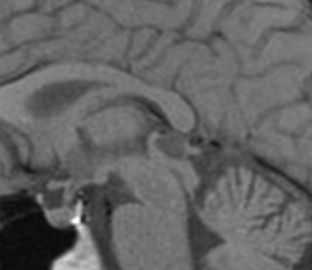

Эпидермоидные кисты (эпидермоиды) - доброкачественные врождённые образования. Они происходят из эктопических эпидермальных клеток и развиваются в период закрытия, в 3-5 нед. эмбриогенеза, как следствие неполного разделения нейрональной и покровной эктодермы. Частота составляет около 1% от внутричерепных образований. Обычно диагностируются в возрасте 25 - 45 лет. Локализация эпидермоидов может быть любой, но типичная - мосто-мозжечковый угол (третье по частоте образование этой области), предмостовая цистерна, параселлярная область, четверохолмие и желудочковая система, очень редко в полушариях, спинном мозге и интрадиплоидно. Растут они интра- или экстрадурально, экспансивно, медленно, сдавливая ствол мозга, внутричерепные нервы, но не разрушая кость. Иногда захватывают сосуды и нервы. По характеру роста их можно отнести к опухолевидным образованиям. Вокруг эпидермоидов нередко развивается асептическое воспаление, а при разрыве содержимое (жир, кератин) прорывается в ликворные пространства. Клинические проявления зависят от локализации и масс-эффекта.

При МРТ головного мозга картина неспецифическая и зависит от содержимого кисты. Если она не содержит жира, то имеет ликворную интенсивность сигнала . В таком случае эпидермоидная киста трудно отличима от арахноидальной, хотя, как правило, не столь однородная. На МРТ типа FLAIR и диффузионно-взвешенных МРТ изображениях содержимое эпидермоидов светлее ликворного. Жировое содержимое, такие эпидермоиды еще называют холестеатомой, приводит к высокому сигналу на Т1-взвешенных МРТ головного мозга. Видимо, он обусловлен липидами, но не холестеролом. На Т2-взвешенных МРТ головного мозга он менее интенсивен чем ликвор. Контуры эпидермоидов всегда четкие. Холестеатомы составляют всего 3-5% от эпидермоидов. В 15-20% случаев встречается кальцификация по переферии кисты. Редко наблюдается контрастирование стенок.

При МРТ головного мозга картина неспецифическая и зависит от содержимого кисты. Если она не содержит жира, топри МРТ головного мозга эпидермоидная киста имеет ликворную интенсивность сигнала. В таком случае эпидермоидная киста трудно отличима от арахноидальной, хотя, как правило, не столь однородная. На FLAIR томограммах и диффузионно-взвешенных МРТ головного мозга содержимое эпидермоидов светлее ликворного. Жировое содержимое, такие эпидермоиды еще называют холестеатомой, приводит к высокому сигналу на Т1-зависимых МРТ головного мозга. Видимо, он обусловлен липидами, но не холестеролом. На Т2-взвешенных МРТ головного мозга он менее интенсивен чем ликвор. Контуры эпидермоидов на МРТ всегда четкие. Холестеатомы составляют всего 3-5% от эпидермоидов. В 15-20% случаев встречается кальцификация по переферии кисты. Редко наблюдается усиление стенок кисты при МРТ головного мозга с контрастированием.

МРТ головного мозга. Т2-взвешенная аксиальная МРТ. Эпидермоидная киста в области предмостовой цистерны слева.